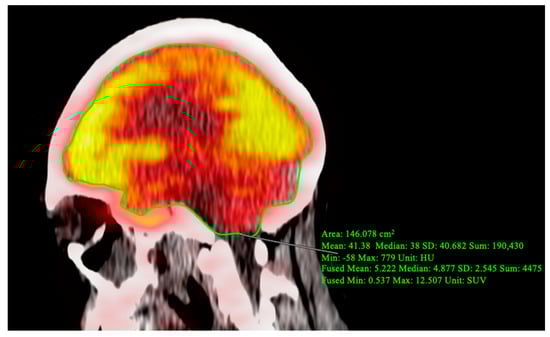

OsiriX MD was also utilized to perform global assessment of FDG uptake in the brain. CT-based segmentation of cerebral and cerebellar regions of interest were determined using precise anatomical landmarks visible on the fused PET/CT images. Specifically, regions were manually delineated on each sagittal slice (Figure 2). To analyze FDG regional uptake in the brain, quantitative regional analysis was conducted with MIMneuro version 7.1.5 (MIM Software, Inc., Cleveland, OH, USA) through validated methods [11,12]. PET data were mapped on a voxel-to-voxel basis to a standard brain template designed for comparison with an integrated anatomical brain atlas featuring predefined ROIs (Figure 3).

Figure 3.

Quantitative assessment of FDG-PET/CT slices interpreted by MIMNeuro. (A) Grayscale axial views of FDG-PET/CT. (B) PET/CT shows low FDG uptake, represented by purple and blue contours, in several critical regions. (C) FDG-PET/CT shows low uptake in the medial temporal lobe (yellow), cerebellum (red), and brainstem (blue).

Brain FDG-PET/CT demonstrated decreased global brain metabolism, with an average SUVmean of 3.42 when compared to the average of 7.59 SUVmean for a cohort of 38 patients at increased cardiovascular risk. Furthermore, regional hypometabolism was observed, particularly in the brainstem (z score = −1.95), medial temporal lobe (z-score = −1.81), cerebellum (z–score = −2.13), hippocampus (z-score = −2.13), inferior frontal gyrus (z-score = −3.53), lateral orbital gyrus (z-score = −3.24), and putamen (z-score = −2.47).